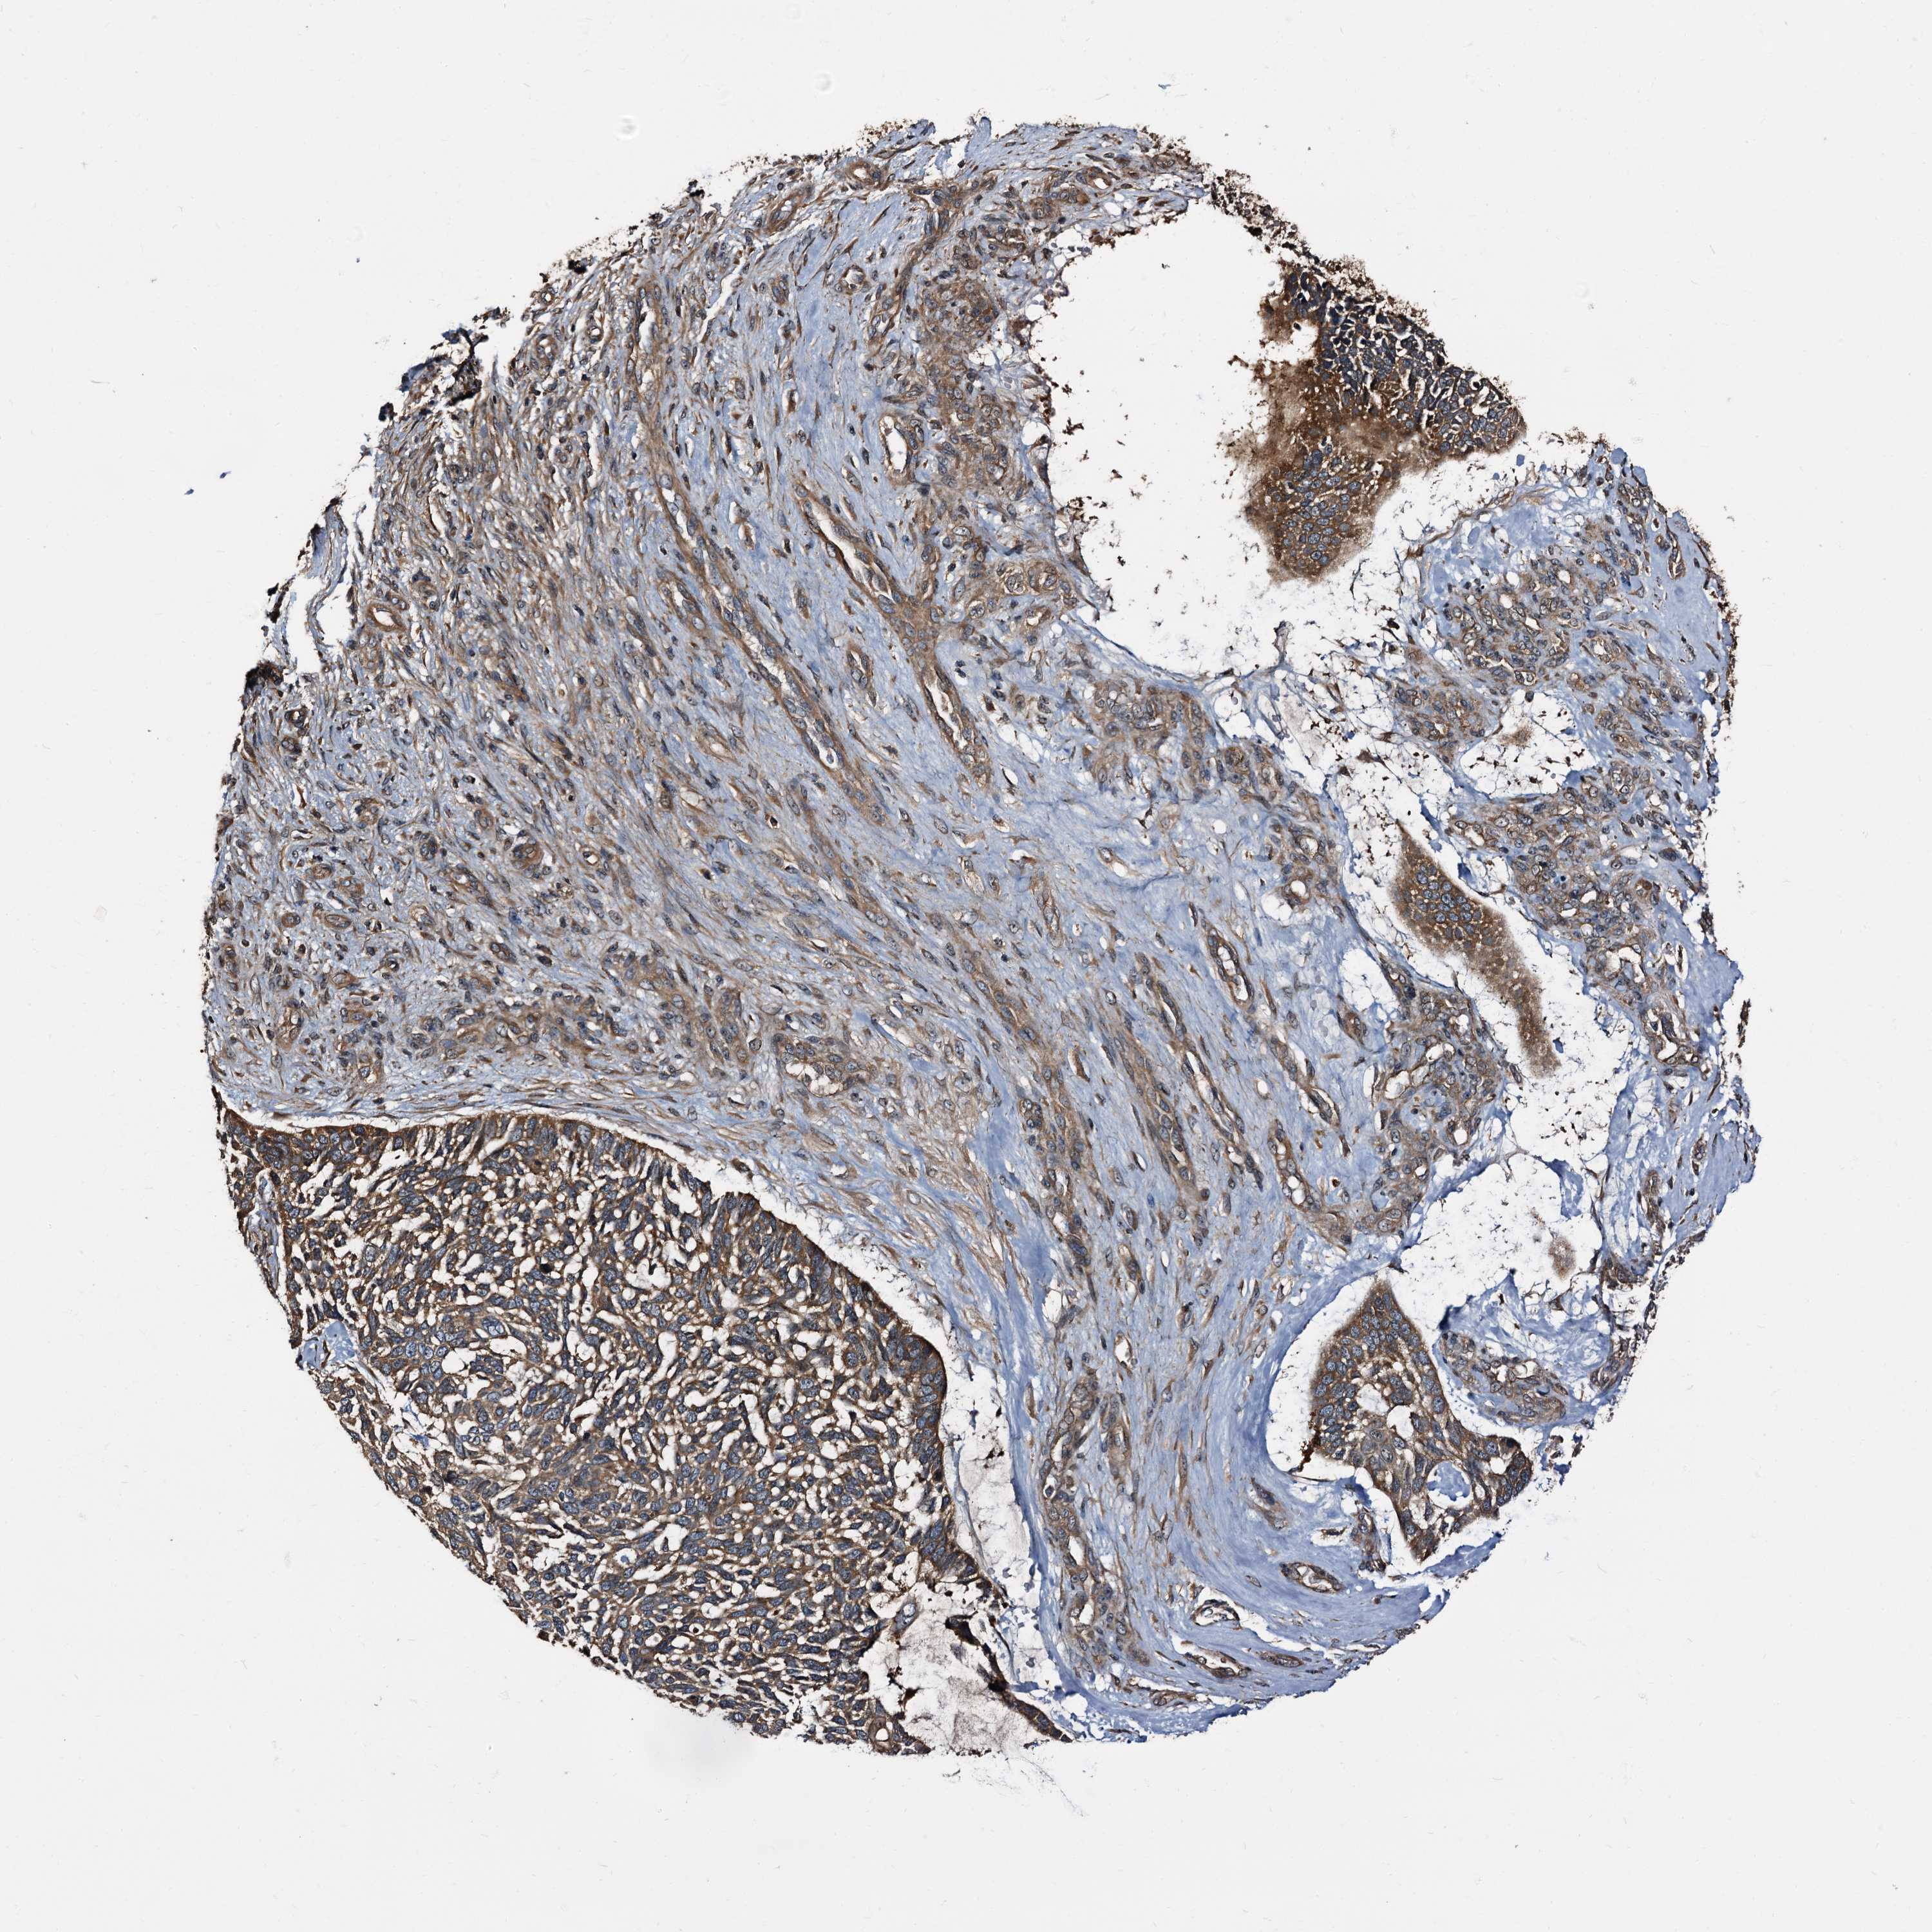

SKIN CANCER - Protein expressioni

A mouse-over function shows sample information and annotation data. Click on an image to view it in a full screen mode. Samples can be filtered based on level of antibody staining by selecting one or several of the following categories: high, medium, low and not detected. The assay and annotation is described here.

Each image is clickable and will lead to virtual microscopy that enables deeper exploration of all samples and also displays staining intensity scores, fraction scores and subcellular localization as well as patient and tissue information for each sample.

Antibody HPA039260

Squamous cell carcinoma, NOS